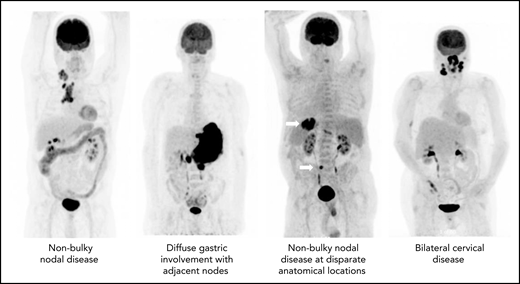

The precise definition of LS-DLBCL is not standardized. Although it is clear that localized disease is restricted to Ann Arbor stages I to II, variation among studies exists in definition of bulk (maximum dimension ranging between 5 and 10 cm), inclusion of B symptoms, and staging methodology. Although not always explicitly stated, LS-DLBCL generally implies disease that can be readily encompassed within a reasonable RT field, as historically RT was considered a mainstay of therapy (Figure 1).7-12